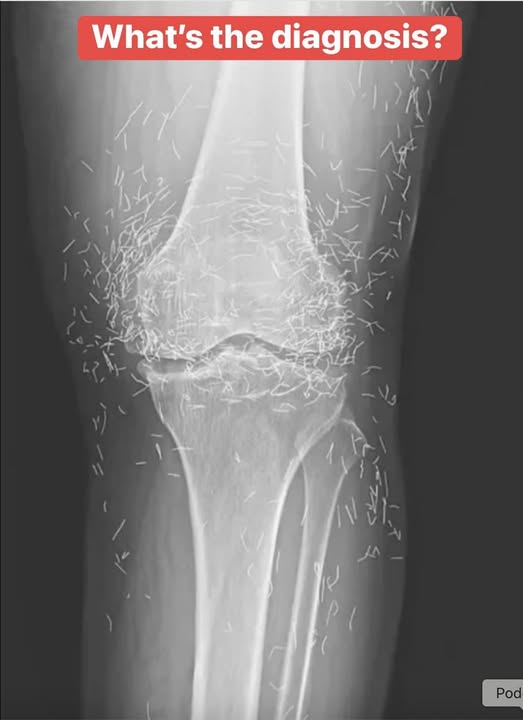

Doctors Shocked by What They Found Hidden Inside a Woman’s Knee X-Ray

What began as a routine hospital visit for knee pain turned into a shocking medical mystery. A 65-year-old woman in South Korea expected a simple arthritis diagnosis—but when her X-ray appeared, doctors were stunned. Her knee joint was filled with dozens of tiny gold needles, leaving everyone wondering how they got there and why they hadn’t been discovered sooner.